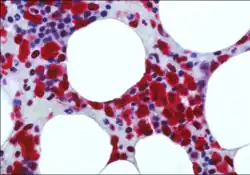

NPM1 immunostaining